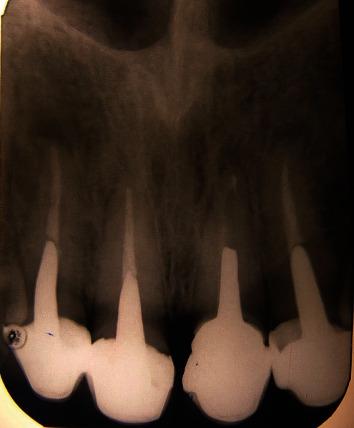

The management of teeth with deep caries, fracture, or perforation in the cervical third of the root is an integral part of dental practice. Orthodontic extrusion preserves the natural root system and may convert the tooth indicated for extraction into useful tooth with good prognosis and a low risk of failure. Orthodontic tooth eruption can be an alternative to treatment such as surgical crown lengthening, especially in esthetic areas, and provides more favorable conditions for prosthodontic coronal restorations by guaranteeing proper sealing and esthetics and preserving periodontal tissue health. The aim of this case report was to explain a multidisciplinary approach that successfully preserve and treat the teeth with subgingival carious lesion. This innovative method is cost-effective and can be easily done with the equipment available in any office.

对患有深龋、牙根折断或牙根颈部三分之一处穿孔的牙齿进行处理是牙科实践的一个重要组成部分。正畸牵引保留了天然的牙根系统,并且可以将原本需要拔除的牙齿转变为预后良好且失败风险低的可用牙齿。正畸牙齿萌出可以替代诸如外科冠延长术等治疗方法,特别是在美学区域,并且通过确保适当的封闭和美观以及保持牙周组织健康,为修复冠修复提供了更有利的条件。本病例报告的目的是阐述一种成功保留和治疗伴有龈下龋损牙齿的多学科方法。这种创新方法具有成本效益,并且使用任何诊所都具备的设备即可轻松完成。